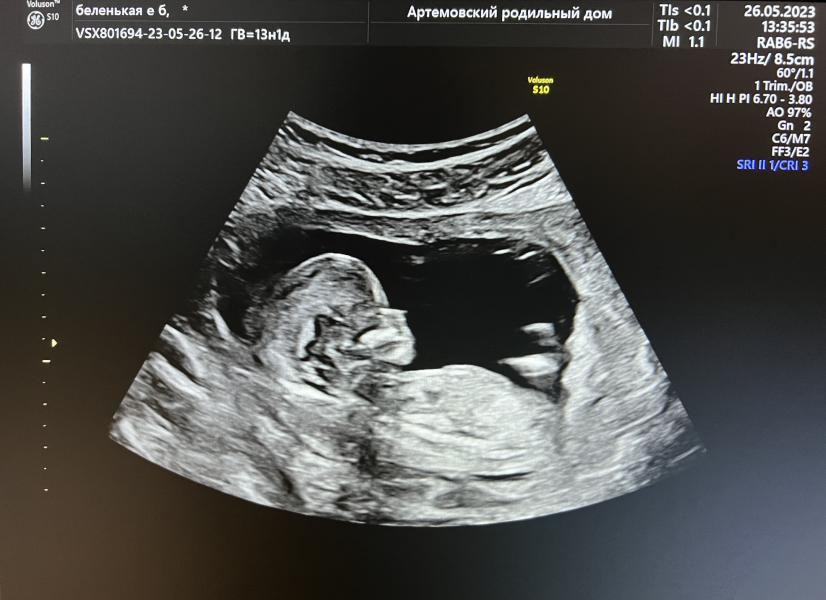

УЗИ на 14 неделе беременности: обсчитались со сроком, растем дальше! Что показало первое узи?

26.05.23 состоялось наше первое узи и сказали, что нам уже не 13 недель, а 14😅 - видимо овуляция началась раньше, сказала врач.

Ну что ж, обсчитались на недельку)) растем дальше🥰